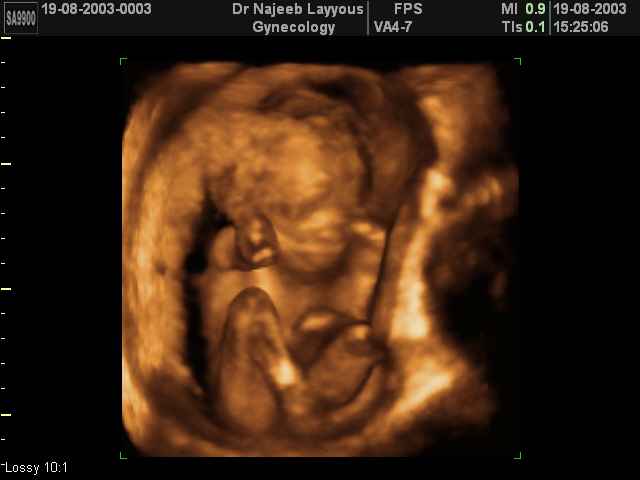

- Fetal Behavior Ultrasound Photos

Ultrasound Photos in 3D showing Fetal Behavior Inside the uterus | Dr N Layyous